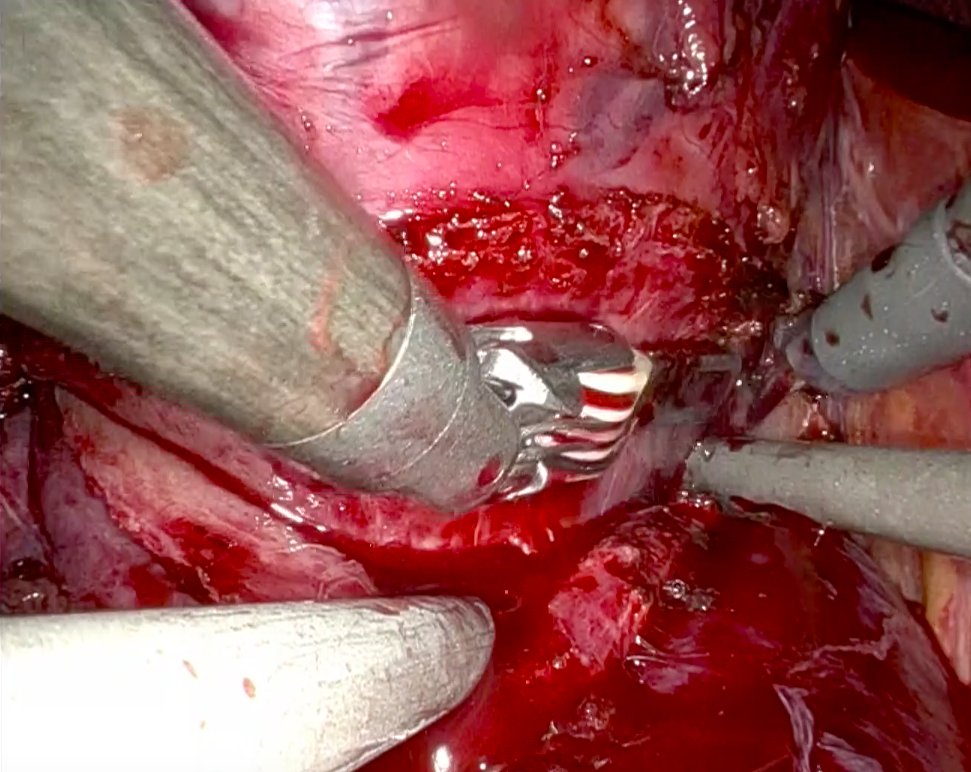

New Edition Verona 13-14 June 2025 Cadaverlab Hands On in Laparoscopic Urological Surgery for the School of Residency in Urology, Sapienza University of Rome. Surgical procedures for radical nephrectomy and radical prostatectomy trainees. Sapienza Policlinico Umberto I European Association of Urology (EAU)

5th Cadaverlab hands on Laparoscopic surgery SAPIENZA UNIVERSITÀ Urologic Residency School ROME. Procedures performed by Residents III IV year: radical nefrectomy - radical prostatectomy. Focus on surgical anatomy and Laparoscopic steps in Major surgery. Sapienza Università di Roma